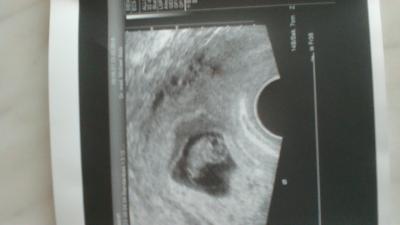

Komme grade vom fa alles war super mein baby ist toll gewachsen und die andere fruchthöle bildet sich auch toll zurück ohne Komplikationen Habe ja 2 kaiserschnitte gehabt trotz dem will der Arzt meinen Wunsch auf eine normalen Geburt ernst nehmen und meinte natürlich können wir es versuchen da es meine letzte ss sein wird habe ich beschlossen Bildchen ist natürlich auch dabei :-)

Bild zu Total Happy :-) - Schwanger - wer noch? Rund um die Schwangerschaft